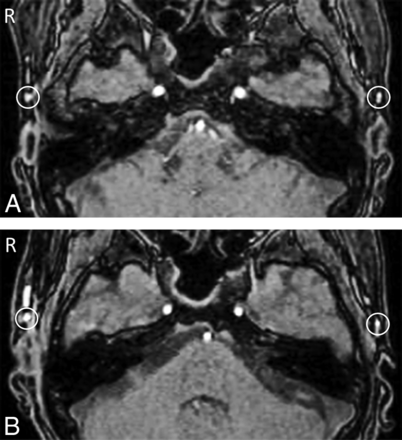

Preoperative (A) and postoperative (B) time-of-flight MR angiography in a case in which cerebral hyperperfusion syndrome was observed after left superficial temporal artery–middle cerebral artery anastomosis. Bilateral regions of interest were manually placed on the parietal branch of the STA immediately after branching the frontal branch of the STA on the same axial image at the axial sections of TOF-MRA; the signal intensity of the graft from the parietal branch of the STA increased postoperatively (B) compared with preoperatively (A).

Preoperative (A) and postoperative (B) time-of-flight MR angiography in a case in which cerebral hyperperfusion syndrome was not observed after left superficial temporal artery–middle cerebral artery anastomosis. Bilateral ROIs were manually placed on the parietal branch of the STA immediately after branching the frontal branch of the STA on the same axial image at the axial sections of TOF-MRA; the signal intensity of the graft from the parietal branch of the STA did not increase postoperatively (B) compared with preoperatively (A).